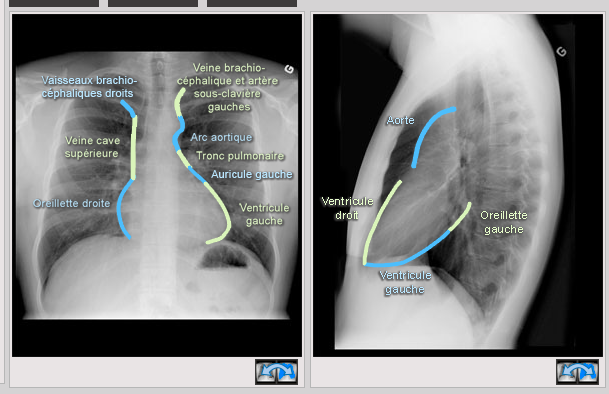

Décrire la silouhette cardio-médiastinale sur une radio